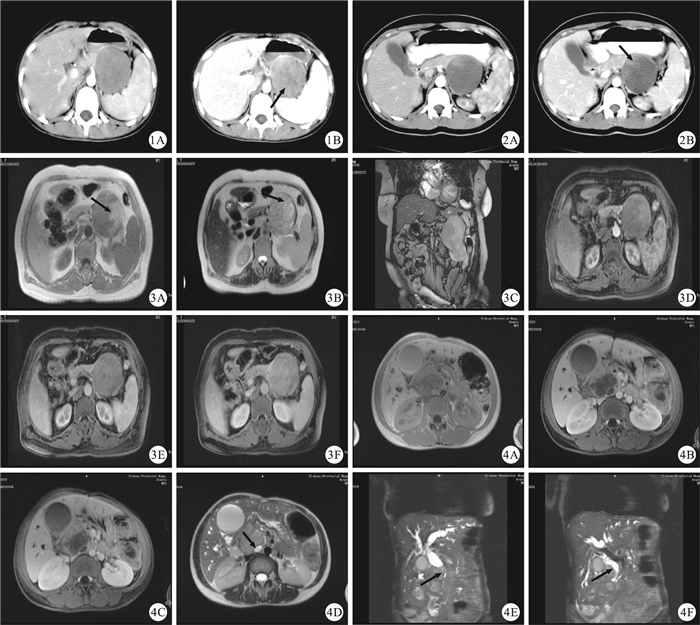

行CT檢查的4例患者腫瘤均呈囊、實性改變;2例囊性成分為主的腫瘤CT平掃表現為不均勻低密度團塊影,其中1例實性成分位于腫塊邊緣呈“壁結節”樣改變,1例實性成分位于腫瘤中心呈“浮云征”;1例腫瘤囊、實性成分基本相仿,表現為囊、實性成分相間分布的混雜密度團塊影;1例腫瘤以實性成分為主,表現為不均勻稍低密度團塊影,囊性成分位于腫塊中心,呈低密度。CT三期動態增強掃描腫塊實性成分表現為動脈期輕度強化、門靜脈期及延遲期漸進性強化,強化程度低于正常胰腺實質,囊性部分不強化。3例行MRI檢查的患者,1例腫瘤以囊性成分為主,T1W圖像上囊性成分表現為低信號、實性成分位于腫塊邊緣呈稍低或等信號,T2W上囊性成分為高信號、周邊實質呈等或稍高信號,腫塊包膜完整,T1W及T2W圖像上均表現為較粗線狀低信號影。2例患者腫瘤囊、實性成分基本相仿,其腫塊內有出血,囊、實性成分分界不清。囊性成分1例表現為在T1W圖像上呈稍高信號、T2W圖像上呈為稍低、稍高混雜信號,1例表現為T1W上呈稍低信號內混雜點片狀高信號、T2W圖像上呈稍高信號內混雜小片狀稍低信號;實性成分1例腫瘤表現為在T1W圖像上呈稍低信號、T2W圖顯上呈等或稍高信號,1例表現為在T1W圖像上呈稍低或等信號中混雜小片狀高信號影、T2W圖像上呈等或稍高混雜信號;1例腫塊內可見T1W及T2W均呈低信號的分隔影。2例伴有腫瘤內出血病例局部包膜欠完整。MRI多期動態增強掃描實性成分、包膜及分隔均表現漸進性強化,囊性成分各期均不強化,增強掃描囊、實性成分分界趨于清楚。具體見圖 1~圖 4。